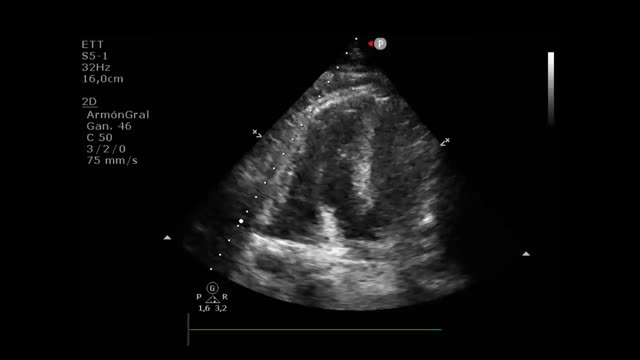

Todas las válvulas protésicas generan un cierto grado de obstrucción comparadas con las nativas, dependiendo del diseño, del tamaño y de la posición anular (intra/supra) de las misma, asemejando una estenosis. Es recomendable consultar los gradientes esperados para el diámetro y modelo de prótesis (Apéndices 1 y 2)31-35. Por ello, puede ser difícil diferenciar la obstrucción hemodinámica de una disfunción leve patológica y del desacoplamiento prótesis-paciente (DPP) o mismatch (tabla 3, fig. 4, Video 4 en material suplementario)36.

En posición aórtica, la morfología triangular del contorno de la velocidad Doppler, con un tiempo de aceleración corto, nos informa de normofunción. Conforme avanza la obstrucción, la morfología de la velocidad Doppler se volverá más redonda, alcanzando el flujo máximo más tardío (fig. 4).